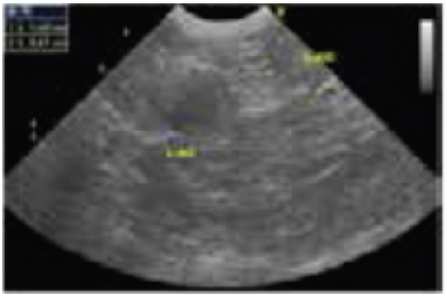

Ecografía abdominal:

Se identificó una masa en el lado craneal de la glándula suprarrenal izquierda (Figura 1).

Figura 1

Sobre la base de los resultados obtenidos a partir de la estimulación con ACTH y la ecografía abdominal, se diagnosticó hipercortisolemia debido al tumor en el lado craneal de la glándula suprarrenal izquierda. Aunque se le recomendó al propietario proceder a la extracción del tumor, no se recibió su consentimiento debido a la edad del perro. Por lo tanto, se aumentó la dosis del trilostano como un método de tratamiento médico. Como resultado de este tratamiento, el nivel de ALT disminuyó y se estabilizó posteriormente.